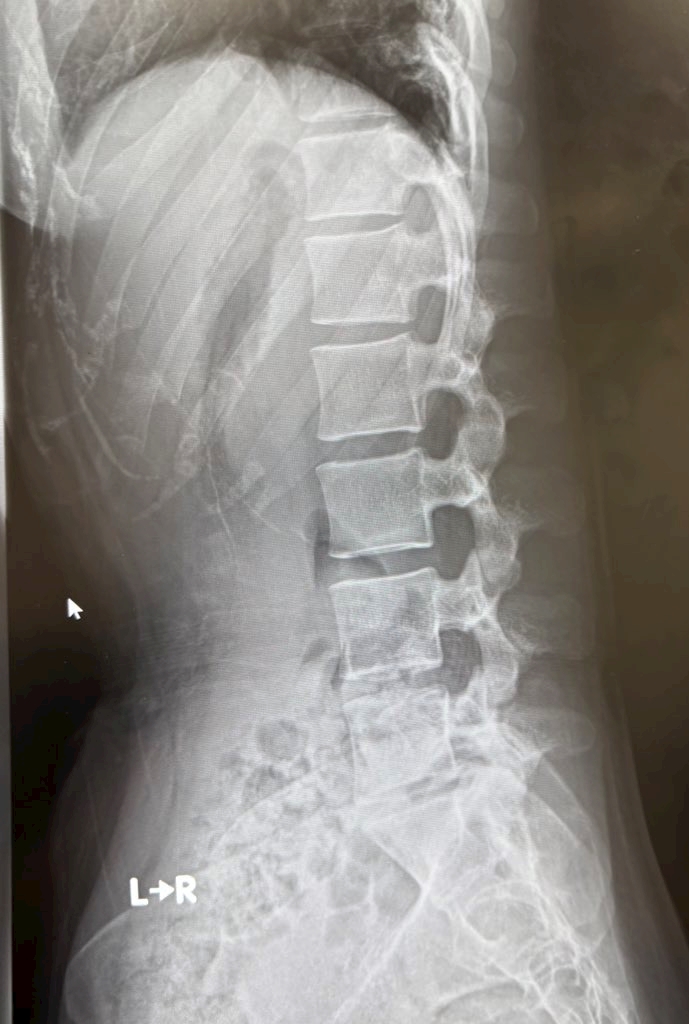

ヘルニアなりまちた🥲

ヘルニアってやつです🥲

レントゲン撮ったら

フラットバック?ってやつも

発覚しました

通常S字カーブの背骨が

かりんちゃまの場合

とんでもなく真っ直ぐなのだ!